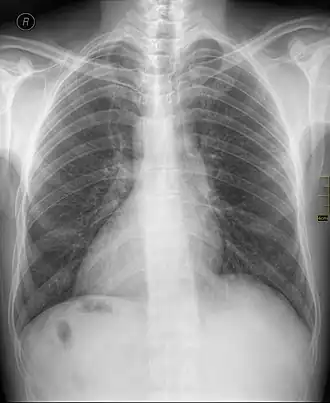

| Raio-X de um paciente com Dextrocardia. Com ele, é possível reparar que o coração aponta para a direita, e não para a esquerda. | |

Dextrocardia é uma anomalia congênita relativamente rara em que o coração está virado para o lado direito do corpo. Pode ocorrer de forma isolada (Situs Inversus solitus) ou junto com outros órgãos (Situs Inversus totalis). Estão associados com um risco aumentado de diversas doenças, mas cerca de 90% dos casos não apresentam sintomas perceptíveis.[1]